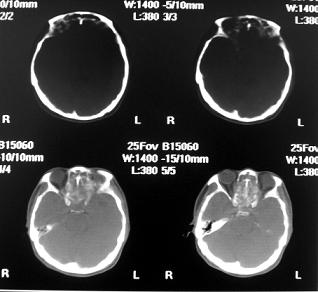

标题: CT10521:男。32岁,副鼻窦ct,请会诊。

男。32岁,鼻塞,流涕一年余。

考虑鼻腔内翻性乳头状瘤,筛窦、上颌窦炎症。建议进一步检查。

软组织密度影填满上颌蚪 筛窦及鼻腔,并导致筛骨 上颌窦内侧壁明显骨质破坏。多考虑:内翻性乳头状瘤!

鼻窦炎伴息肉形成可能,上颌窦内侧壁明显骨质破坏并无挤压,膨胀改变,多不考虑内翻性乳头状瘤.

双侧鼻腔内低密度软组织影,骨壁无明显破坏,鼻腔无扩大,双侧上颌窦、筛窦软组织影,窦壁增厚,结合临床考虑鼻息肉合并慢性上颌窦炎。